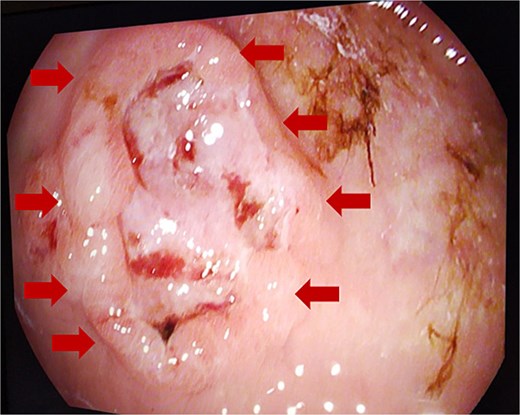

The patient presented for the third time, after 4 years of initial diagnosis, with a soft tissue mass in the right gluteal and posterior femoral region. Wide resection was performed revealing two tumor masses. The tumor of the right gluteal region weighted 21 g and measured 4 × 3.5 × 2.5 cm with surrounding fat tissue. On cross-section, the tumor measured 2.5 cm. Microscopically, it was composed predominantly of spindled cells in a herringbone pattern, with areas of necrosis and hemorrhage, as well as larger, more pleomorphic cells with hyperchromatic nuclei. The resection from the posterior femoral region weighed 235 g, measuring 12.5 × 6.5 × 5.5 cm, containing a 9.5 × 4.5 × 5 cm tumor surrounded by skeletal muscle. The tumor was with the described morphology and presence of a high grade pleomorphic component. Immunohistochemistry showed a diffuse CD10 positivity. The tumor cells were negative for Desmin, SMA, Caldesmon, and CD56 (Fig. 2) During the postoperative period, he was continuously anemic Er 2.6 × 1012/L; hemoglobin 81 g/L; hematocrit 0.23|L/L, which indicated further investigations. Gastroscopy was performed and an ulcerative lesion was measuring 2 cm located on the front gastric wall near the great curvature (Fig. 3).

Gastric biopsies revealed tumor infiltration of pleomorphic tumor cells with bizarre nuclei and mitotic figures that showed positivity only for Vimentin and CD10, and a diagnosis of metastatic high grade sarcoma was made (Fig. 4). Due to blood loss and severe anemia the patient was admitted to University Clinic for abdominal surgery. Bimanual palpation determined the lesion to be localized to the grater curvature of the stomach at the transition from the corpus to the antrum. A wedge resection was made of the segment that contained the lesion with a GIA stapler without compromising the permeability of the stomach. The post-operative course was settled and quickly established per os feeding (Fig. 5). One week after the resection, due to symptoms of melena, the patient was investigated by colonoscopy where a polypoid lesion measuring 4.5 cm was found in the right colon (coecum) (Fig. 6). It was surgically removed by a short right colectomy, and histology confirmed as high grade sarcoma metastasis. To the best of our knowledge, this is the first case of gastric and colon metastasis from soft tissue high-grade sarcoma.